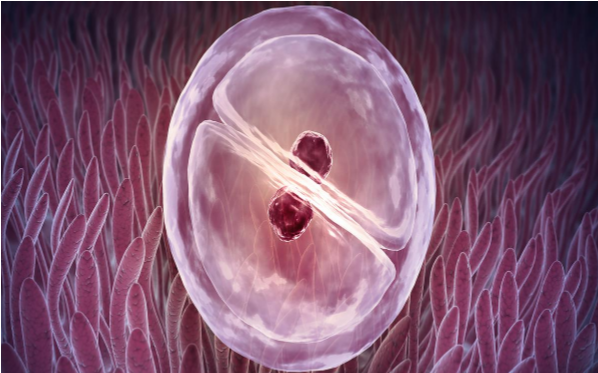

泰国试管婴儿技术成熟,医疗水平高,且费用相较于其他发达国家更经济实惠。目前,许多泰国医院都拥有先进的设备和经验丰富的医护团队,提供全方位的生育辅助服务,包括促排卵、胚胎移植、基因检测等。

泰国试管婴儿的成功率一般在50%-70%之间,具体取决于多个因素,例如女性年龄、卵巢功能、男性的精子质量等。 此外,医院的技术水平和医生的经验也对成功率有重要影响。